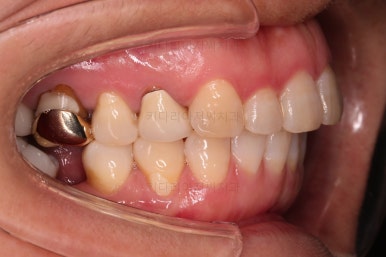

초진 시 입안의 모습입니다.

아랫니 큰 어금니 하나가 없어서 임플란트를 원하셨던 환자분이셨어요.

앞니가 조금 삐뚤고, 아랫니는 사이사이에 틈새가 있었지만 전체적인 교정은 원치 않으셨어요.